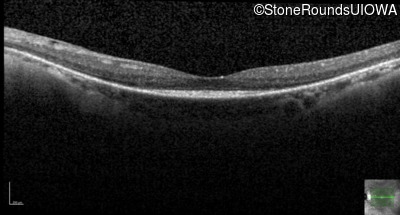

Optical Coherence Tomography - Left - 20/25

Exemplar / OCT Stack